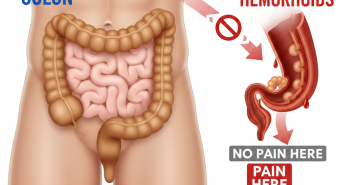

Introduction Colon cancer screening tests are designed to find cancer early or prevent it by…